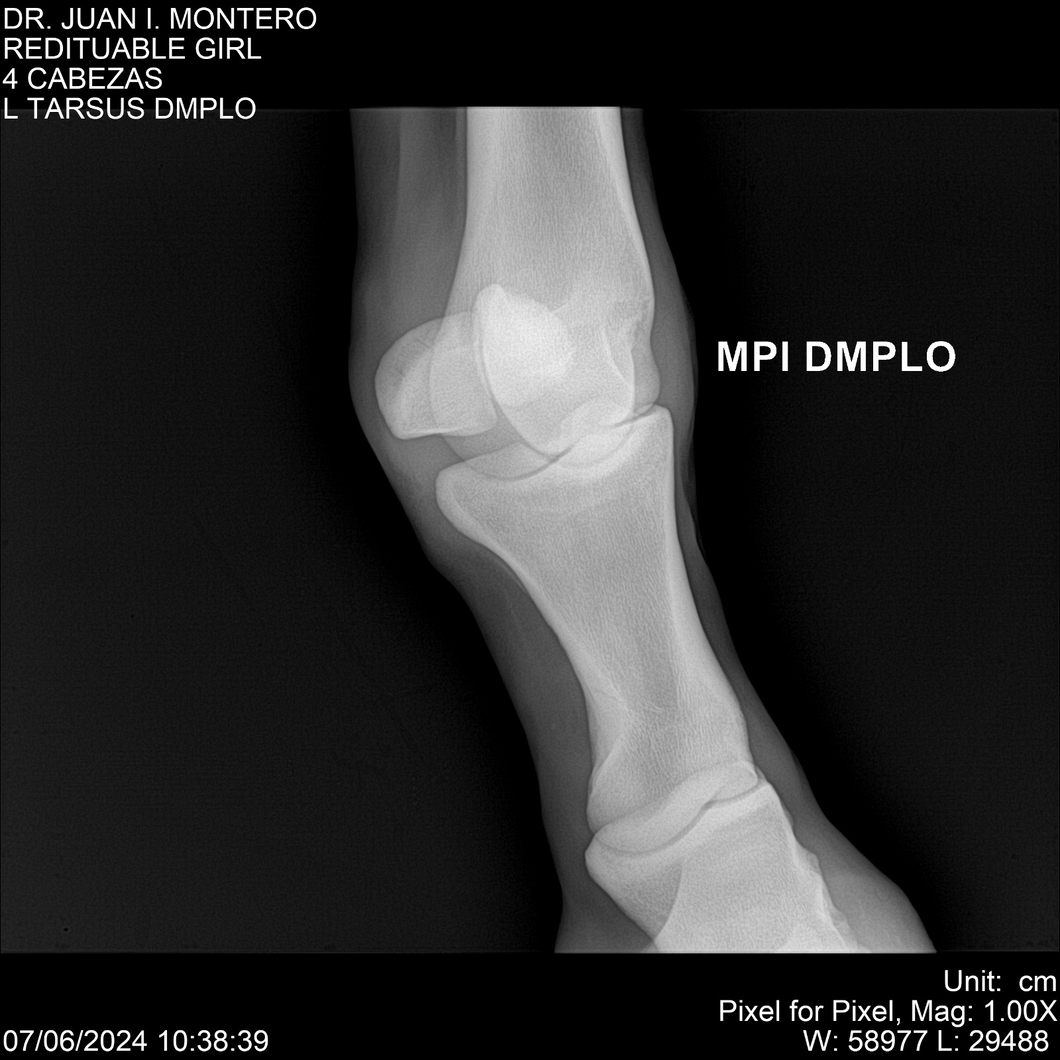

LOTE 19, REDITUABLE GIRL Lote Anterior Volver al remate Lote Siguiente Ficha Contacto Montevideo - Ficha del Lote Identificador: #281096 Categoría: Yeguarizos Montevideo - 79 Visualizaciones ClicData Contacto Empresa: Abelenda N. R., Walter Hugo Nombre*: Teléfono* : E-mail* : Mensaje Enviar Registrese gratis Este contenido Exclusivo está disponible sólo para usuarios registrados Ingresar